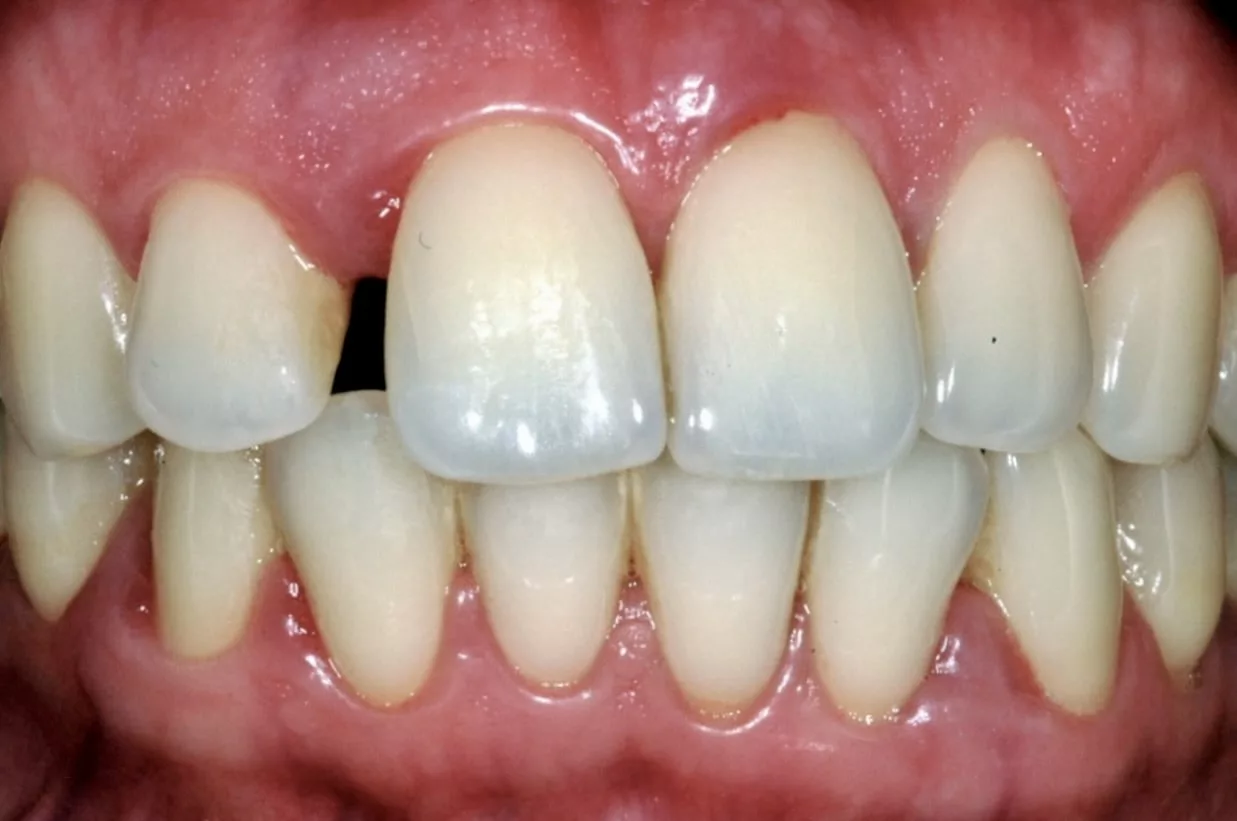

Une anesthésie locale pourra être administrée afin d’améliorer le confort du patient.

En cas de mobilité dentaire prononcée, des contentions pourront être réalisées afin d’immobiliser les dents concernées et apporter un confort de vie au patient.